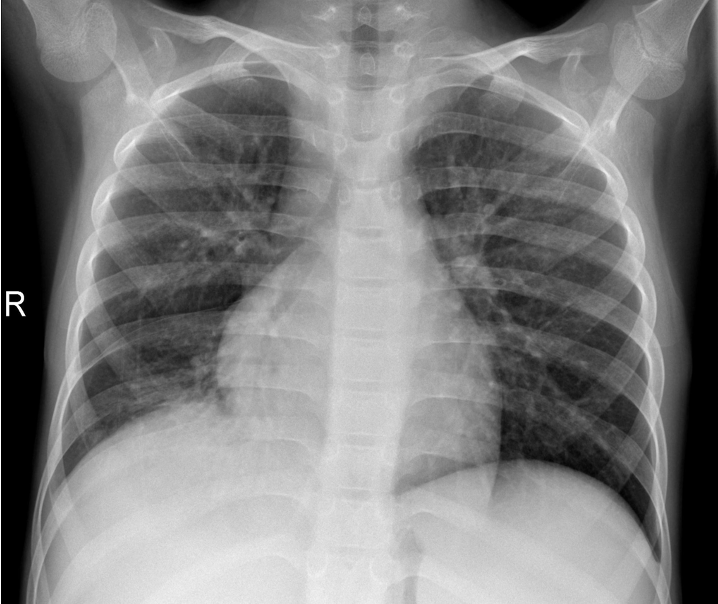

Figure 2 exemplifies two healthy lungs (upper two) and two lungs suffering from pneumonia (lower two). All images of the data set are recorded with different resolutions. Therefore, we convert the images to greyscale and compress them to 128128 pixels. We allocate 1,500 images to the training set, 200 to the validation set, and 1,400 to the test set.